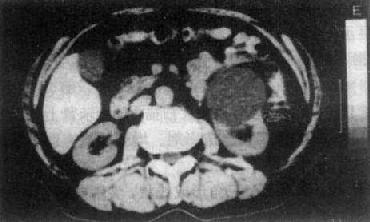

膀胱癌

图4-4-10 膀胱癌

膀胱腔内突起的肿块(白↓),

肿瘤已侵犯至壁外(黑↑)